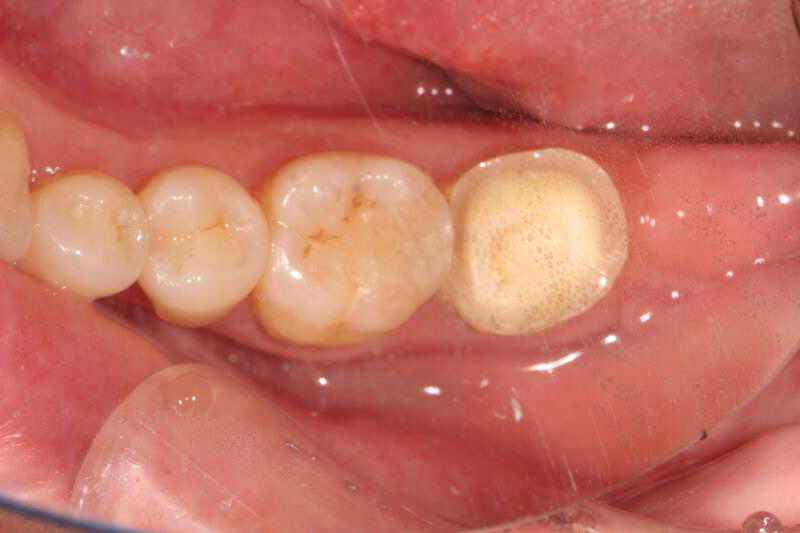

今天给大家分享的病例是一位中年女性,17缺失,由于长时间未修复,47伸长,留给17修复的空间不足。

老卢给她的治疗方案是:17种植修复,47根管治疗后截冠、高嵌体修复。这样可以最大限度的增加患者的咀嚼效率。

由于患者喉反射比较严重,种植牙冠和高嵌体都是用我们德国进口CEREC扫描制做的哦,与传统取模相比大大降低了不适感。